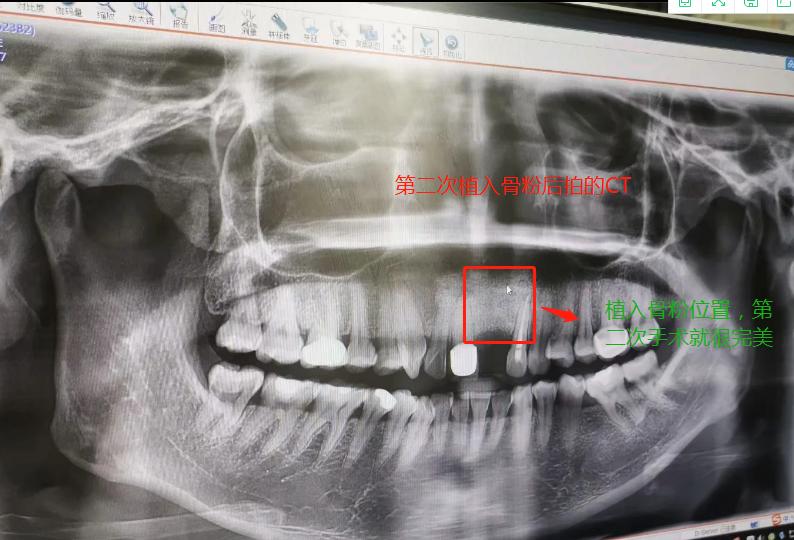

第二次做完植入手术后拍的CT

2019年7月27日做了种植骨粉手术,在医院要等半个小时留意一下是否有出血情况,没有就可以回家休息。做手术是自己一个人坐地铁来回的,勇敢吧。第一天嘴里都是血,第二第三天也是,脸也肿起来,也会有一点点骨粉掉出来,我那几天都是喝粥和喝汤,第四天才敢吃饭,第七天伤口就好了,可以带上临时假牙,因为我是上颚门牙,上颚骨头密度没有那么好,正常要等4个月左右,我的骨粉还是种植的,不是自身的骨头,所以必须要等半年才能种种植牙。等到2020年1月26日去种植牙根的时候,那个主任已经调去别的分店,第一次补完骨粉我就发觉里面还有个小洞,问医生里面为什么有个洞的,医生说没事的。我打算去分店种植牙齿的,以为跟我那个医生会比较了解我情况,后来那个的助理叫我不要去分店弄了,在这里安排个专家给我看。经过专家的诊断,我还有个洞没有补到骨粉,需要再做个补骨粉手术后等半年看看情况能不能种牙再说。我听了真想哭起来,大门牙好不容易空半年可以种牙了,结果还要我补骨粉,还要等那么长时间。经过跟这家医院医生沟通和别的门诊医生回答,决定还是回到这家医院做修复,跟助理谈了价格,他说就收取800元,补0.5克骨粉。于是就开始了第二次手术,第一次手术补了0.5克骨粉(2个单位,0.25克为一个单位),第二次补了0.75克骨粉,本来是0.5克骨粉,医生做手术的时候说还有点间隙,还需要0.25克骨粉,问我要不要加,我说加,就算要另外收费,我也要加,我的牙齿受的折磨太多了。我要好好弄好这颗牙齿,就收了800元,也没有额外收0.25克的骨粉钱。我在这家口腔医院花了6800元种植骨粉,第二次骨粉植入伤口比较大,医生说恢复期要12天,确实7天伤口还是没有恢复的很好。而且今年1月底爆发疫情,1月31日领导就让我们上班,我们公司是做医疗设备。伤口都没有完全康复就坚持上班了。